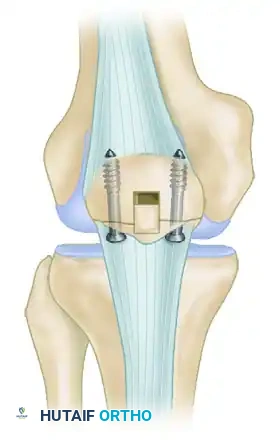

- Internal Fixation: The fracture is reduced and secured using parallel, vertical 4.0 mm partially threaded cancellous screws inserted from distal to proximal through the inferior pole.

- Suture Augmentation: If the bone quality is poor or the fragment is highly comminuted, the fixation can be augmented with heavy nonabsorbable sutures (e.g., No. 5 FiberWire) passed circumferentially through the screw holes or around the screw heads in a tension-band configuration.

- Corticocancellous Slot Graft (Optional but Recommended): To enhance biological healing and provide structural support, an oscillating saw is used to harvest a corticocancellous slot graft (typically 10 mm wide × 15 mm long) from the anterior surface of the proximal patella. This graft is then translated distally across the fracture site.

FIGURE 48-28: Stress fracture of the inferior pole of the patella in a collegiate basketball player. The fracture is secured with parallel screws, and a corticocancellous slot graft is placed distally across the fracture site to promote osteosynthesis.